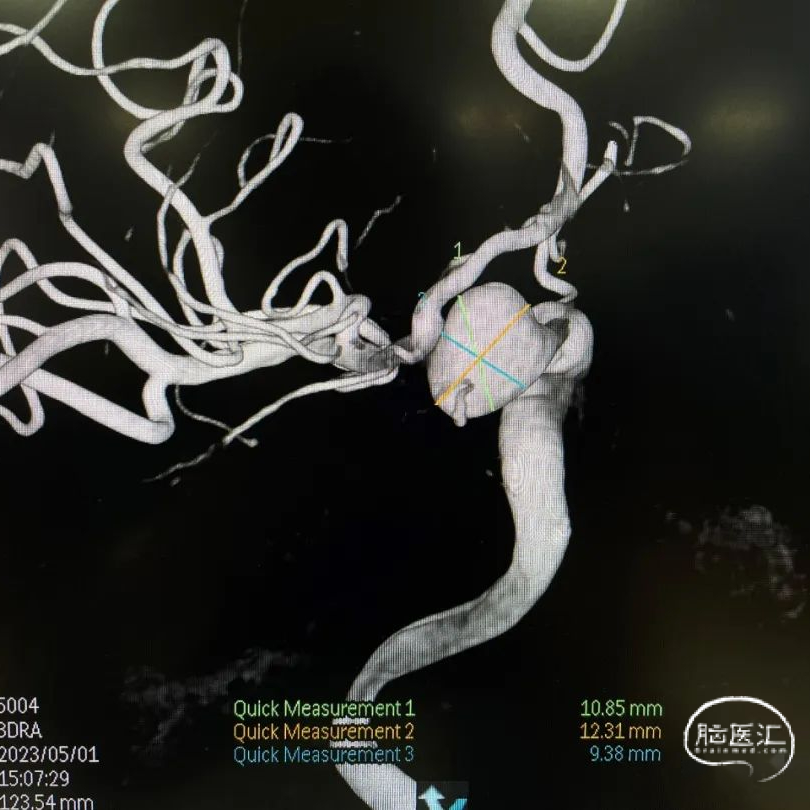

术前DSA造影:造影后发现该患者左侧后交通动脉瘤。

术前DSA造影:颈内动脉C6、7段膨大扭曲,导致C5段与M1之间形成明显的锐角。通过3D工作位测量出左侧后交通动脉瘤大小约为13.5mm*10mm*8mm:动脉瘤最大径13.5mm,载瘤动脉直径:近端5.0mm,远端3.5mm。